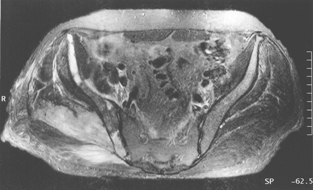

Radiography of his hips, pelvis and lumbosacral spine revealed mild degenerative changes only. A bone scan showed increased uptake in the region of the right buttock, right sacroiliac joint and the superior aspect of the right acetabulum. Computed tomography (CT) scan revealed diffuse swelling involving the right gluteus medius and piriformis muscles (Box, Figure 1). Magnetic resonance imaging (Box, Figure 2) confirmed these findings, but also showed swelling of the obturator internus and part of the gluteus maximus muscles, as well as some increased signal in the right iliac bone seen on T1-weighted images.

When the diagnosis was established, methotrexate was also stopped. The patient presented for CHOP-based chemotherapy (cyclophosphamide, adriamycin, vincristine, prednisolone) 19 days later (2 months after he stopped taking cyclosporin). The palpable swelling of the right buttock had disappeared, and a repeat CT scan confirmed resolution of the previously diffuse muscle swelling (Box, Figure 4). Chemotherapy was withheld.